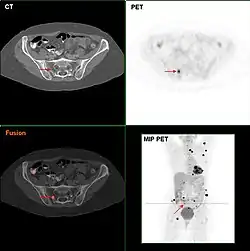

Die Befundung des PET- oder PET/CT-Bildes erfolgt durch Betrachtung der rekonstruierten Schnittbilder (axial, koronar oder sagittal). Bei PET/CT-Geräten ist die Darstellung von PET und CT verknüpft, so dass automatisch die Position des korrelierenden PET-Bildes gezeigt wird, wenn der Bildkursor im CT-Bild verschoben wird.

Für eine Übersichtsdarstellung wird ein sogenanntes MIP-Bild (Maximum Intensity Projection) herangezogen. In dieser Darstellung ist das gesamte Untersuchungsobjekt abgebildet und man erlangt einen schnellen Überblick über Regionen erhöhter Aufnahme. Zur nochmals besseren Visualisierung kann man das MIP um sich selbst rotieren lassen, um das Untersuchungsobjekt von allen Seiten zu zeigen.

Knochenmetastasen

Knochenmetastasen unterschiedlicher Tumorerkrankungen können mit PET/CT sehr gut nachgewiesen werden. Das Verfahren ist sensitiver als die SPECT und erheblich sensitiver als die planare Skelettszintigrafie, jedoch auch aufwändiger und somit teurer. Je nach Tumorentität werden unterschiedliche Tracer verwendet, meist jedoch FDG und Natriumfluorid, beim Prostatakrebs auch 11C- oder 18F-Cholin. Metabolische Aktivität des Tumors ist mit Hilfe des Tracers FDG, die Reaktion des Knochens auf den Tumor mit der Natriumfluorid-PET/CT meist gut darstellbar (siehe Bildbeispiele).[33]

FDG-PET desselben Patienten: Die osteolytische Knochenmetastase im Halswirbelkörper reichert FDG nicht an und ist nur im CT erkennbar. Die beiden weiteren Knochenmetastasen in der Lendenwirbelsäule werden dagegen auch in der FDG-PET/CT dargestellt. -

Natriumfluorid-PET/CT desselben Patienten: Die osteolytische Knochenmetastase in der Halswirbelsäule zeigt einen extremen Uptake und ist klar erkennbar. Die beiden weiteren Knochenmetastasen in der Lendenwirbelsäule stellen sich in der PET/CT-Aufnahme ebenfalls sehr gut dar. -

Vergleich derselben Läsion des vorgenannten Patienten: Die FDG-PET/CT-Aufnahme zeigt die Stoffwechselaktivität des Tumors. -

Vergleich ein und derselben Läsion des vorgenannten Patienten: Die Natriumfluorid-PET/CT-Aufnahme zeigt die Stoffwechselaktivität des Knochens als Reaktion auf den Tumor.